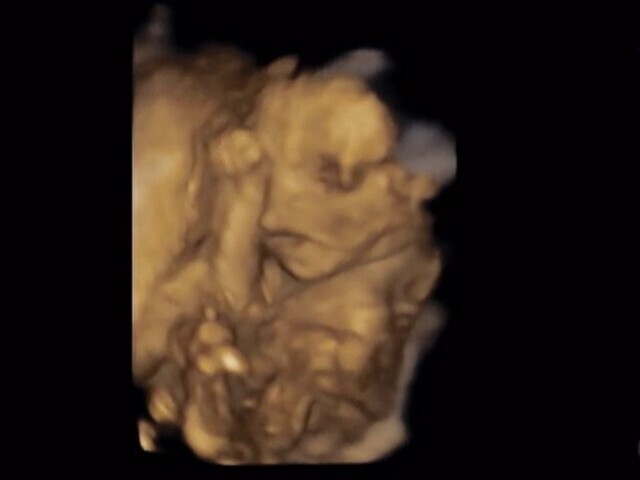

19週1日(19w1d・男の子)|きうらよしこ さん(35歳)

エコー写真撮影時のエピソード:

初めて4Dエコーで我が子を見ることができました。普通のエコーに比べ、鮮明に顔を見ることができ、更に愛しく思えたのを記憶しています。悪阻がきつかったですが、時折写真を眺め、悪阻があるってことは子どもが元気に育っている証拠なんだなぁ等気持ちが前向きになり、どんなお顔なのかな?等話しかけたりしていました。主人も写真を見返しては、どっちに似てるんだろうなぁと嬉しそうに話していました。食事面に関しては、幸い食べ物は何でも食べれたので、あまり神経質にならず好きなものを口にしていました。ですが、出来るだけ自炊をし、赤ちゃんに良いものをと色々ネットで調べて作ったりしました。自分が口にしたものがそのまま我が子へ繋がってるんだなぁ、しっかり栄養とってね等話しかけたりもしてましたね。